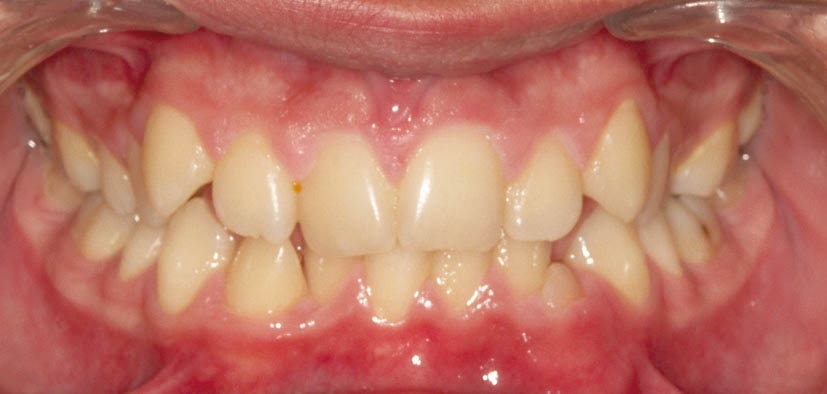

شکل 100-2: نمای روبرو